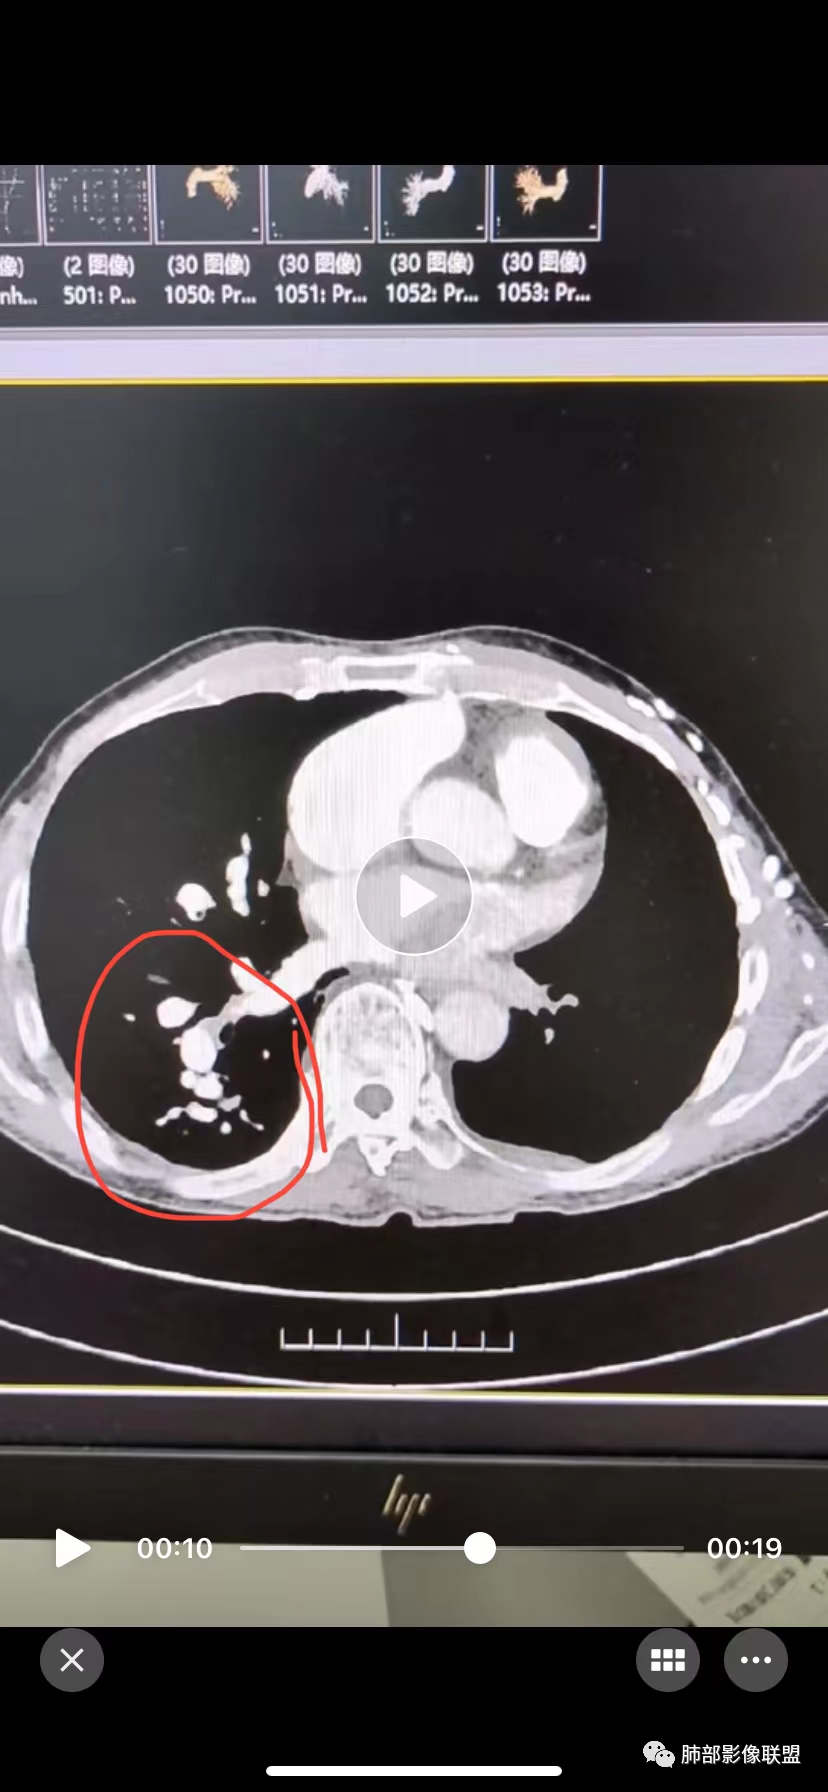

王琰:补充晨读视频

有腹水,皮下水肿,右肾萎缩。没增强

这一坨是什么

南边:

肺动脉

周围区域连续些看,感觉有树芽征。

如果这个树芽征明确的话,这个就不是肺水肿。可以做个最大密度投影或多方位观察再次确定是否有树芽征。弥漫性中轴间质和周围间质增厚常规就两个疾病谱,癌淋或肺水肿。而且这个人有明确的右肺明显。结合可疑树芽征,很多可以看到沿着肺动脉走形的磨玻璃影,需要可疑血源播散性转移或血管源性恶性肿瘤病变,再就是嗜血管的淋巴源性的恶性肿瘤。血管肉瘤,血管内淋巴瘤病可以这个表现,之前还碰见过一个,好像是NK/T淋巴瘤也这个表现,这个有点记不清了。

如果是肿瘤的话,右下肺这一坨怎么解释呢,看着确实是增粗的肺动脉。

肺栓塞完全堵塞的,罕见啊

难得。否继发炎性病变了?难得的好病例。

总感觉肺栓塞解释不了。右肺还有很多其他表现,但是右肺动脉是挺好的。

我的意思是说右肺动脉没有栓塞,不能用肺栓塞一元论解释。右肺动脉很宽也解释不了右肺这么多的病灶表现

@曹冠杰,济医附院?一侧肺栓塞,右心血流到另一侧无栓塞的肺动脉,故而高灌注,可以肺水肿。少见模式,肺栓塞对侧肺水肿。